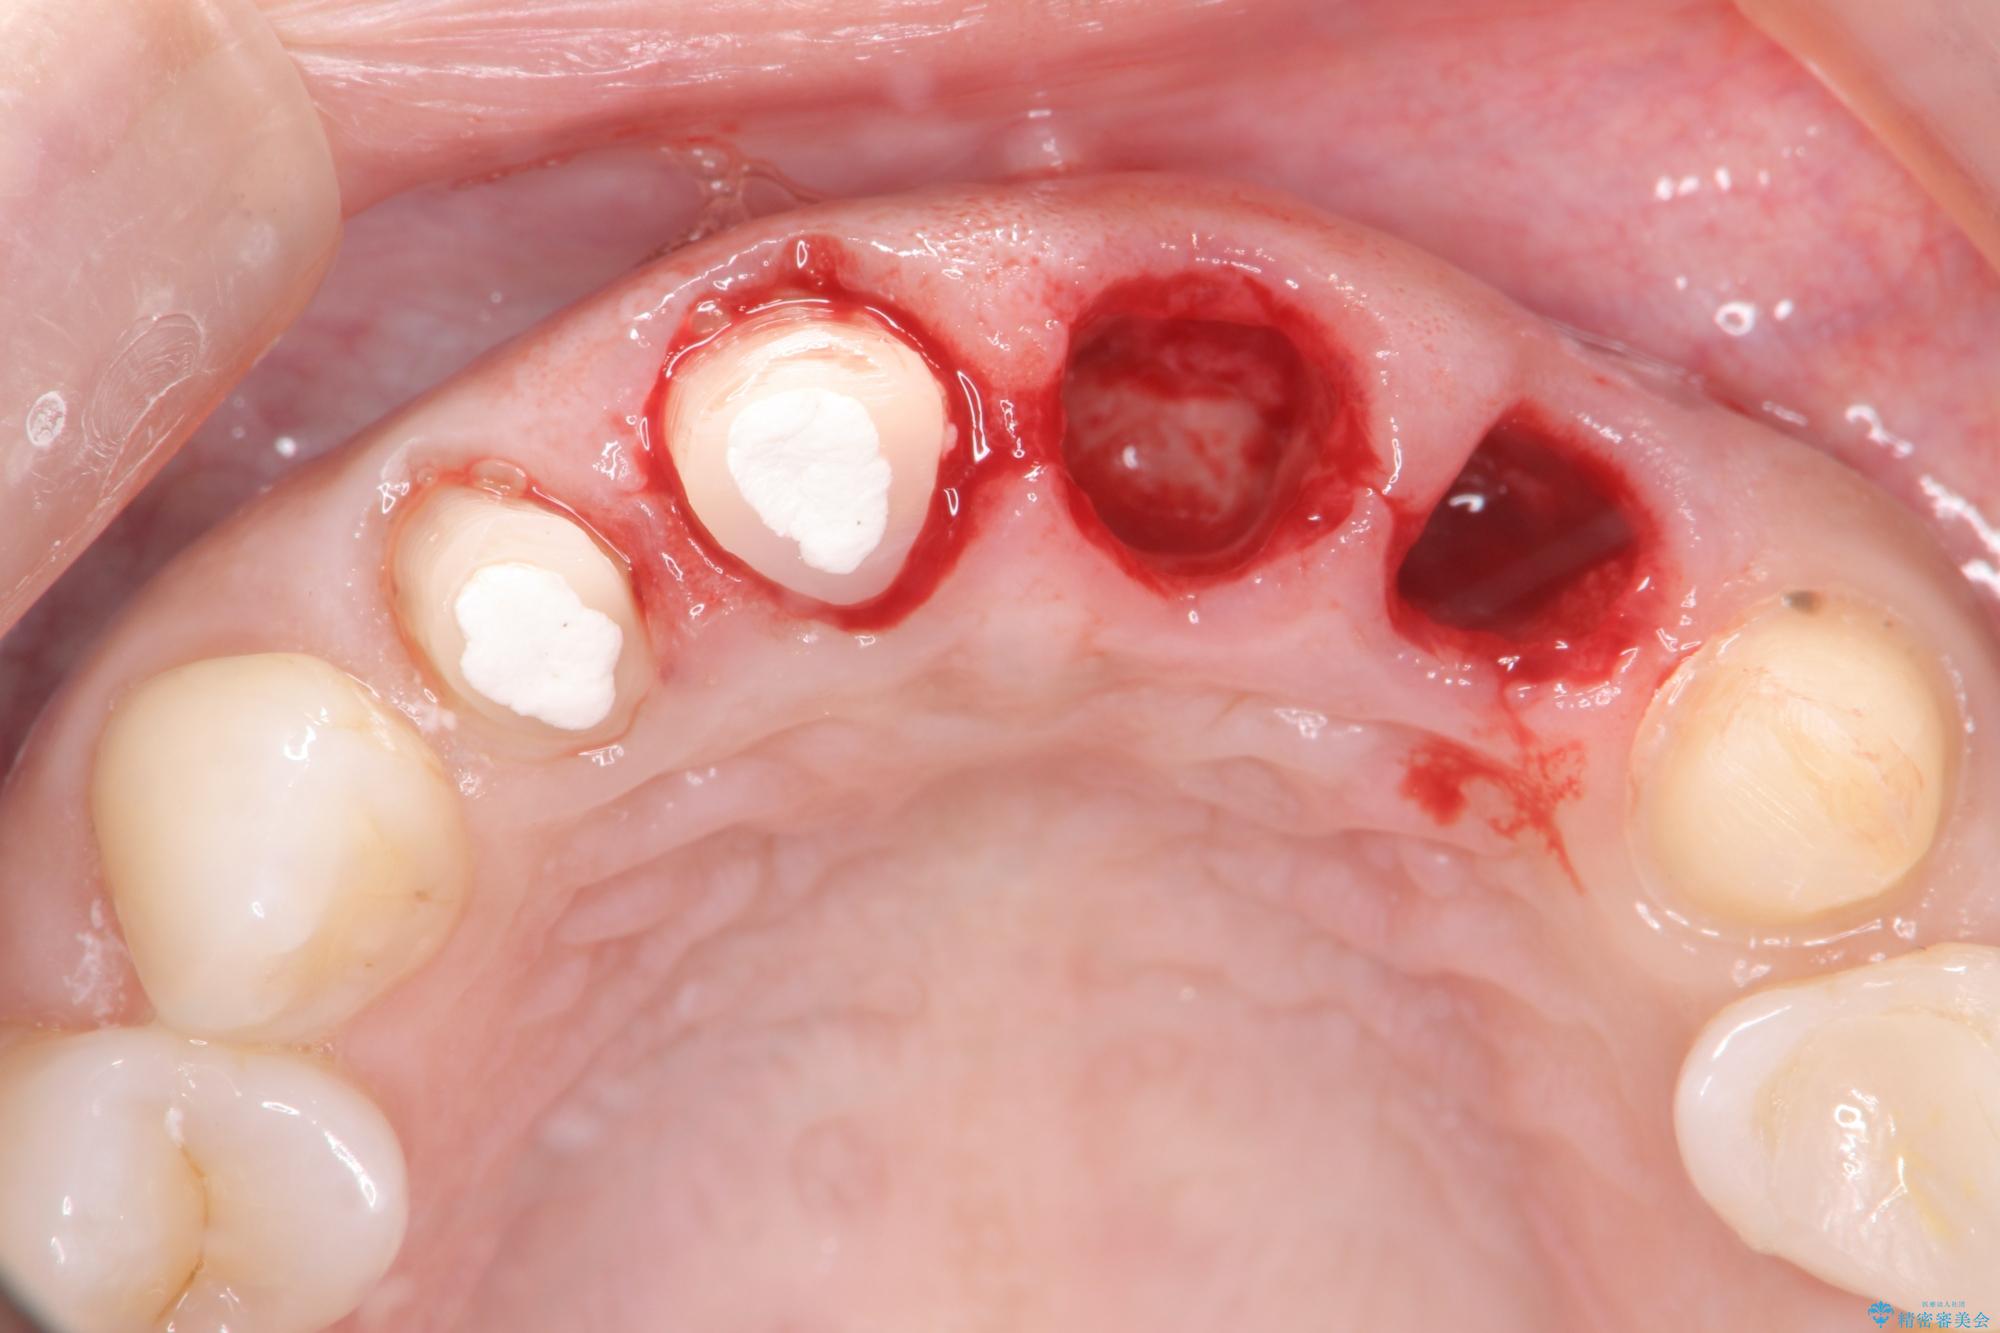

一見して問題ないように見える左側の2前歯は、セラミックを除去してみると亀裂や虫歯の再発が見られました。

抜歯時に可及的に歯肉のボリュームを保つよう骨充填材とコラーゲン製剤による填塞を行い審美的かつ機能的なブリッジとなるよう治療を進めます。

治療中

歯槽堤保存術を併用したブリッジ治療 治療中画像 歯槽堤保存術を併用したブリッジ治療 治療中画像 歯槽堤保存術を併用したブリッジ治療 治療中画像 歯槽堤保存術を併用したブリッジ治療 治療中画像 歯槽堤保存術を併用したブリッジ治療 治療中画像 歯槽堤保存術を併用したブリッジ治療 治療中画像 歯槽堤保存術を併用したブリッジ治療 治療中画像